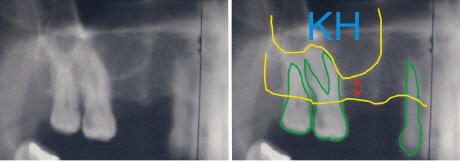

Die gelbe untere Linie entspricht dem Kieferkamm, der bis zur oberen gelben Linie verläuft. Über dieser oberen gelben Linie beginnt die Kieferhöhle (KH). Der Abstand zwischen den beiden gelben Linien zeigt, wie viel vertikaler Knochen (Knochenhöhe) vorhanden ist. Der rote Pfeil zeigt den unzureichenden Knochenabschnitt.

Leider ist es bei zu geringer Restknochenhöhe in Einzelfällen nicht möglich, den Knochen aufzubauen und gleichzeitig die Implantate einzubringen. Der Restknochen ist dann so gering, dass die Implantate für sich alleine nicht primär stabil verankert werden können. In diesen Fällen erfordert die Behandlung einen Schritt mehr. Zuerst wird der Knochen durch die Sinus Lift-Methode aufgebaut. Wenn der Knochen nach 4-5 Monaten eingeheilt ist, werden in einer zweiten Operation die Implantate eingebracht. Man spricht daher auch von einem zweizeitigen Vorgehen, oder auch von einer verzögerten Implantation.